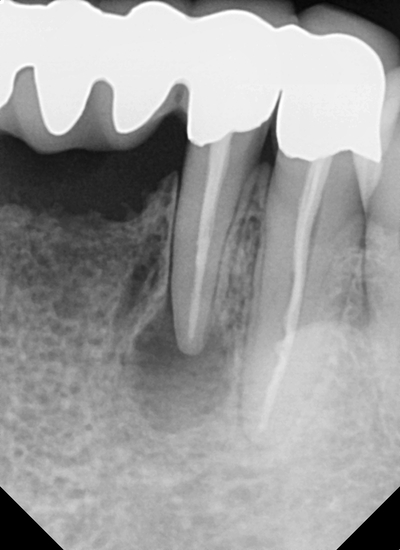

먼저 마취 후 잇몸을 열고 치조골(뼈)을 살짝 삭제합니다.

안에 있는 염증을 모두 제거해 깨끗하게 해줍니다.

치아 끝을 조금 잘라내고

신경치료 시 채웠던 재료를 잘라낸 부분보다 안쪽으로 더 제거해 줍니다.

이제 <MTA> 라는 생체 친화적 재료로 세균감염이 되지 않게

치아 끝부분을 막아준 후 마무리합니다.